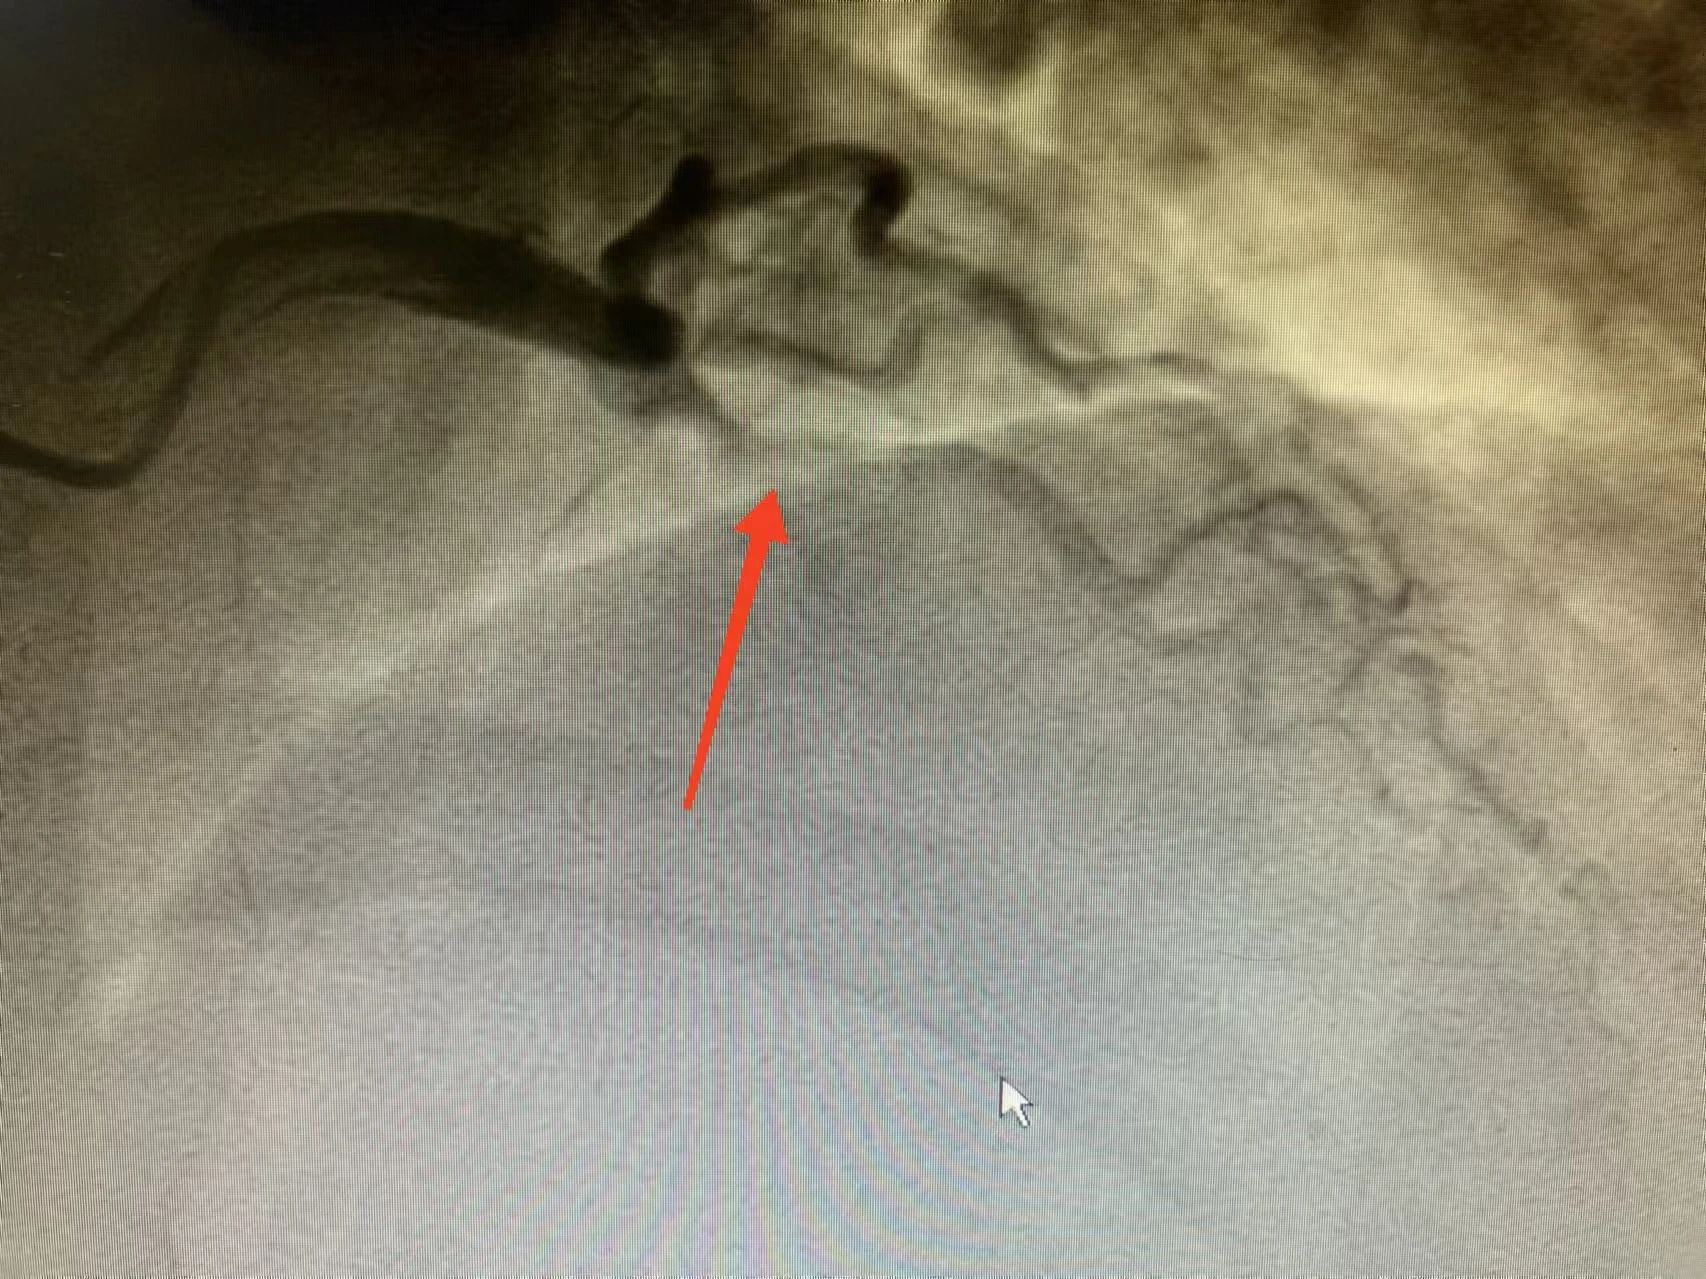

心血管内科主任冯骥、王平得到通知后,马上开通绿色通道,将患者转入心血管内科重症监护病房,同时电话告知家属病情并积极组织抢救。在抢救手术过程中,医院名医工作室专家刘志辉指导行急诊造影,影像显示心脏血管左前降支急性闭塞,立即予以血管开通,成功植入一枚支架。术后前向血流恢复,生命体征稳定。

术前 术后 经过紧急介入手术,患者生命安全得到了有力保障。 回到病房,患者和家属悬着得心终于放了下来。术后查房时,冯骥反复叮嘱患者不能随意停药了。 心血管内科主任冯骥、王平正在查房 心内科专家刘志辉表示,现在是冬天,正是心血管疾病高发的时候。由于冬季人的生理机能反应较慢,经常处于应激状态,从而增加心脏负荷。再加上室内外温差大,血管受到冷空气刺激后突然收缩,导致血流供应中断或血管阻塞,引起急性心肌梗死。尤其是有冠心病病史或“三高”控制不佳的慢性病患者,要养成健康生活习惯的同时,务必规范用药、定期复查,消除心梗危险因素。 景德镇市第一人民医院胸痛中心提醒:发生心梗,不要惊慌,牢记两个“120”,及早前往医院治疗。 第一个“120”,是要及时拨打“120”电话。如胸痛等症状持续15分钟仍没有缓解,应立刻拨打120急救电话。 第二个“120”,是指心梗救治要争取黄金120分钟。并不是说超过120分钟就没有救治的意义了,而是指如能在黄金120分钟内送医救治,可有效缩小心肌梗死范围,大大降低心梗的病死率和致残率。越早进行溶栓、支架等灌注治疗,患者后期生活质量就会更高。